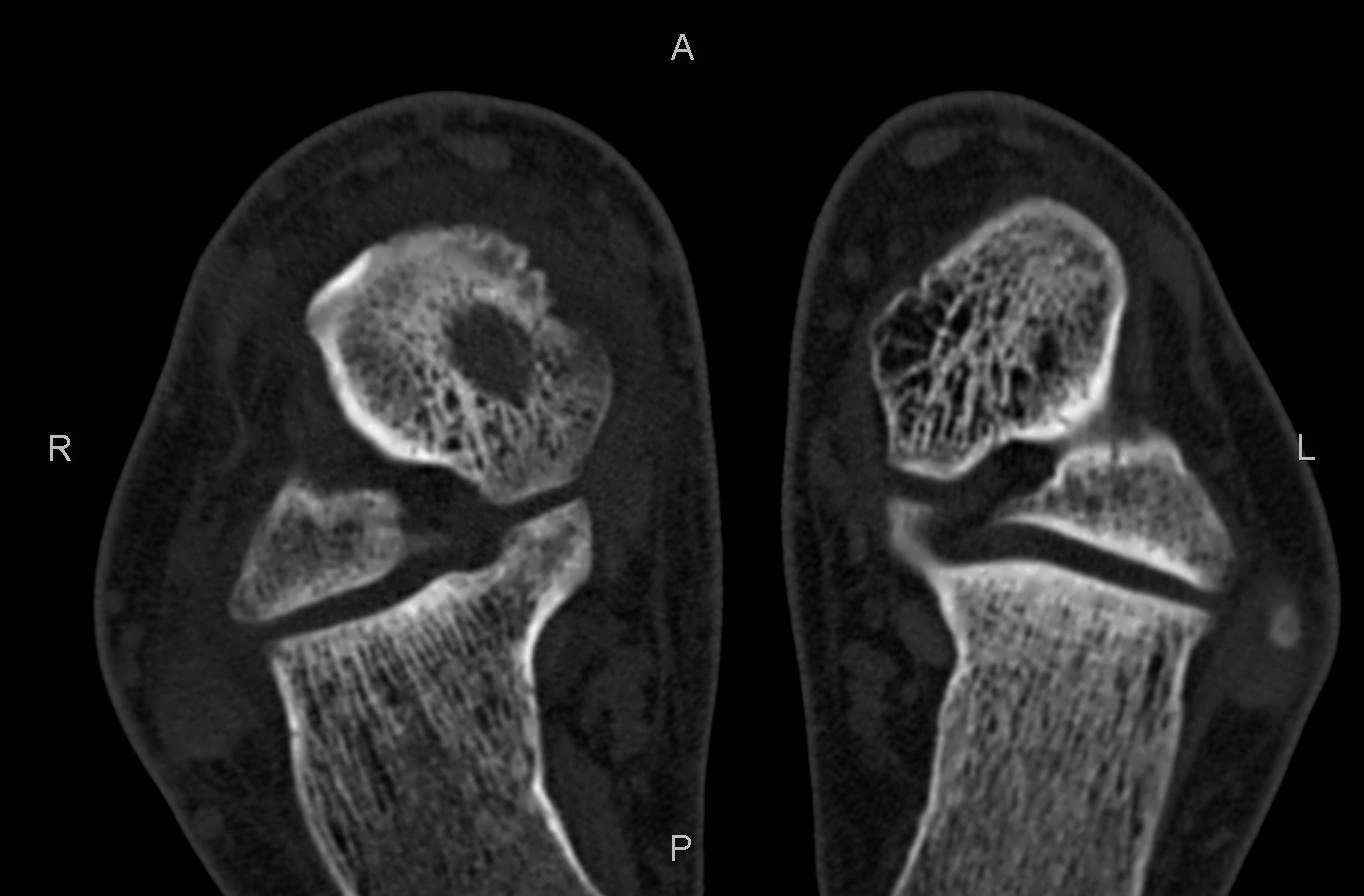

Уважаемые коллеги, обратился за помощью пациент, мужчина, 25 лет. С жалобами на болевой

синдром в области голеностопного сустава и среднем отделе стопы. Травму отрицает. Со слов,

болевой синдром в течении 1 года. Последние 1-1.5 мес периодически вынужден пользоваться

костылями. После ограничения нагрузки боли уменьшаются. Соматически здоров. До появления

болей активно занимался рукопашным боем.

На СКТ картина рассекающего остеохондрита блока

таранной кости, киста шейки таранной кости с признаками импрессии суставной поверхности. А

также - разрастания переднего края б\берцовой кости сопровождающиеся клиникой импиджмент

синдрома.